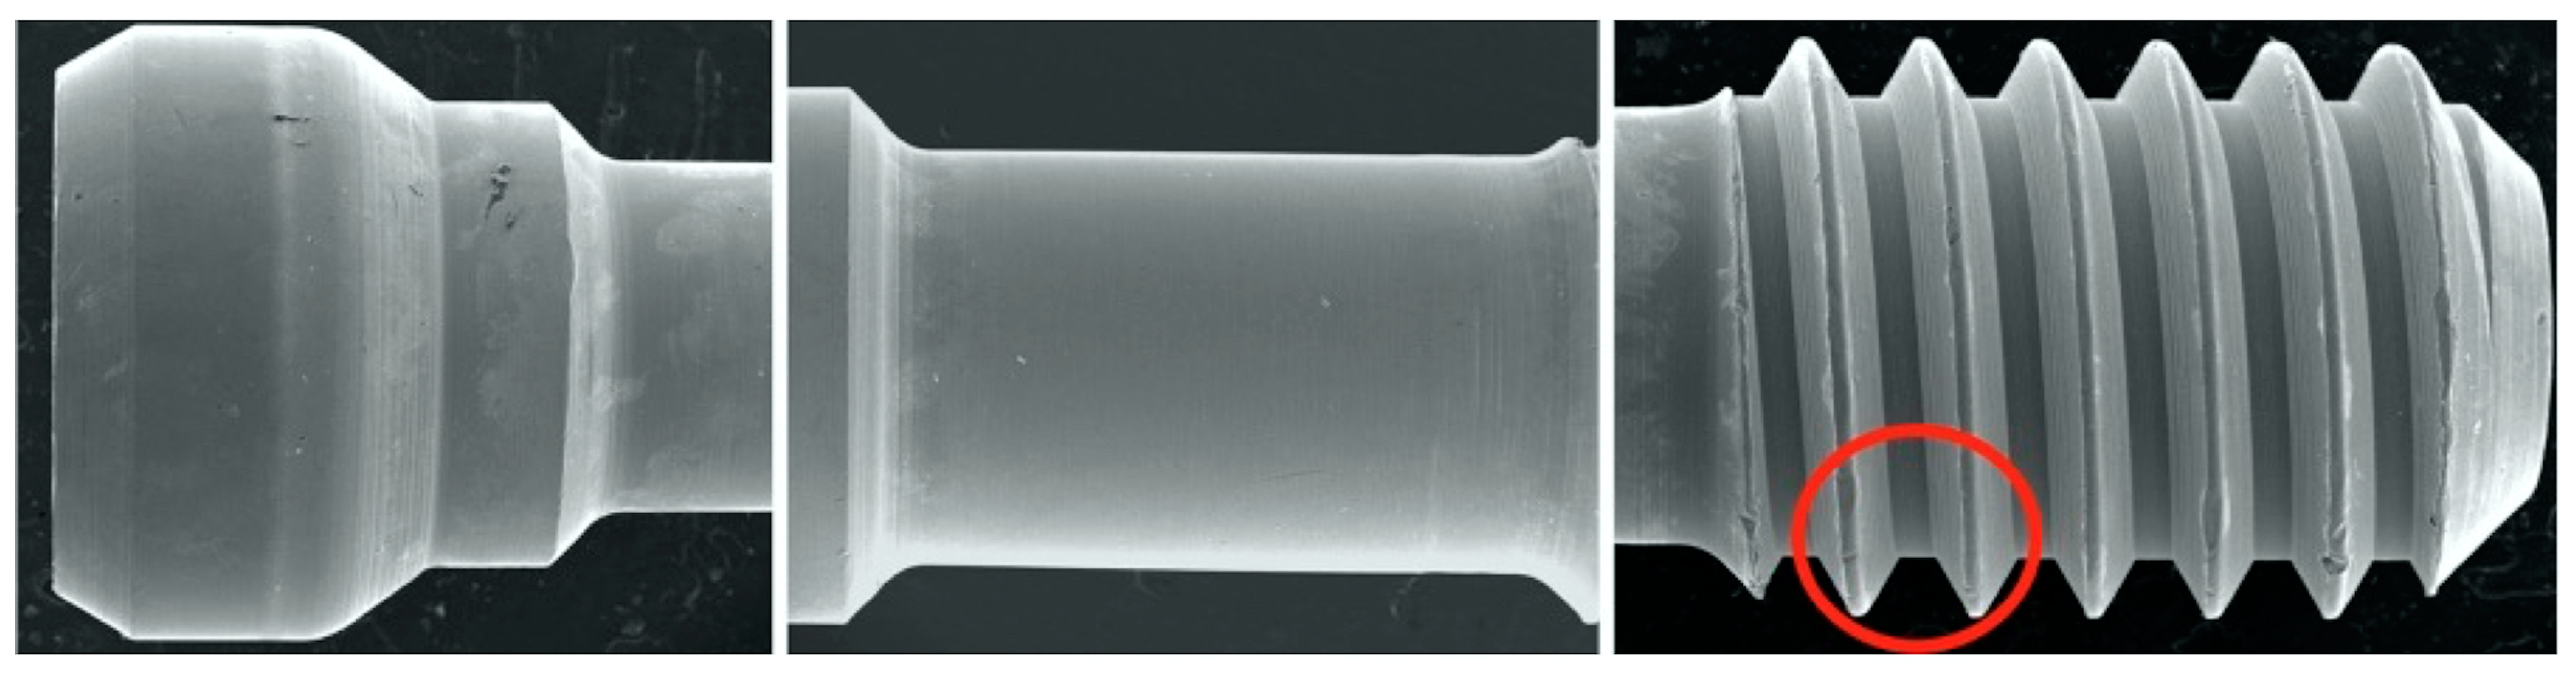

2.2. Scanning Electron Microscopy (SEM)

| After | X | X | X | X | Chips + galling + plastic deformation with thinning of the thread (knife edge) | |||||

- From the SEM qualitative evaluation, there were similar, notable screw morphology changes after CL between the E and NE abutments.

- Yokoyama, K.; Ichikawa, T.; Murakami, H.; Miyamoto, Y.; Asaoka, K. Fracture mechanisms of retrieved titanium screw thread in dental implant. Biomaterials 2002, 23, 2459–2465. [Google Scholar] [CrossRef]

- Guzaitis, K.; Knoernschild, K.; Viana, M.A. Effect of repeated screw joint closing and opening cycles on implant prosthetic screw reverse torque and implant and screw thread morphology. J. Prosthet. Dent. 2011, 106, 159–169. [Google Scholar] [CrossRef]

- Arshad, M.; Mahgoli, H.; Payaminia, L. Effect of repeated screw joint closing and opening cycles and cyclic loading on abutment screw removal torque and screw thread morphology: Scanning electron microscopy evaluation. Int. J. Oral Maxillofac. Implants 2018, 33, 31–40. [Google Scholar] [CrossRef] [PubMed]

- Alzoubi, F.M.; Sabti, M.; Alsarraf, E.; Alshahrani, F.A.; Sadowsky, S.J. Evaluation of two implant-supported fixed partial denture abutment designs: Influence on screw surface characteristics. J. Prosthodont. 2024, 33, 443–451. [Google Scholar] [CrossRef] [PubMed]